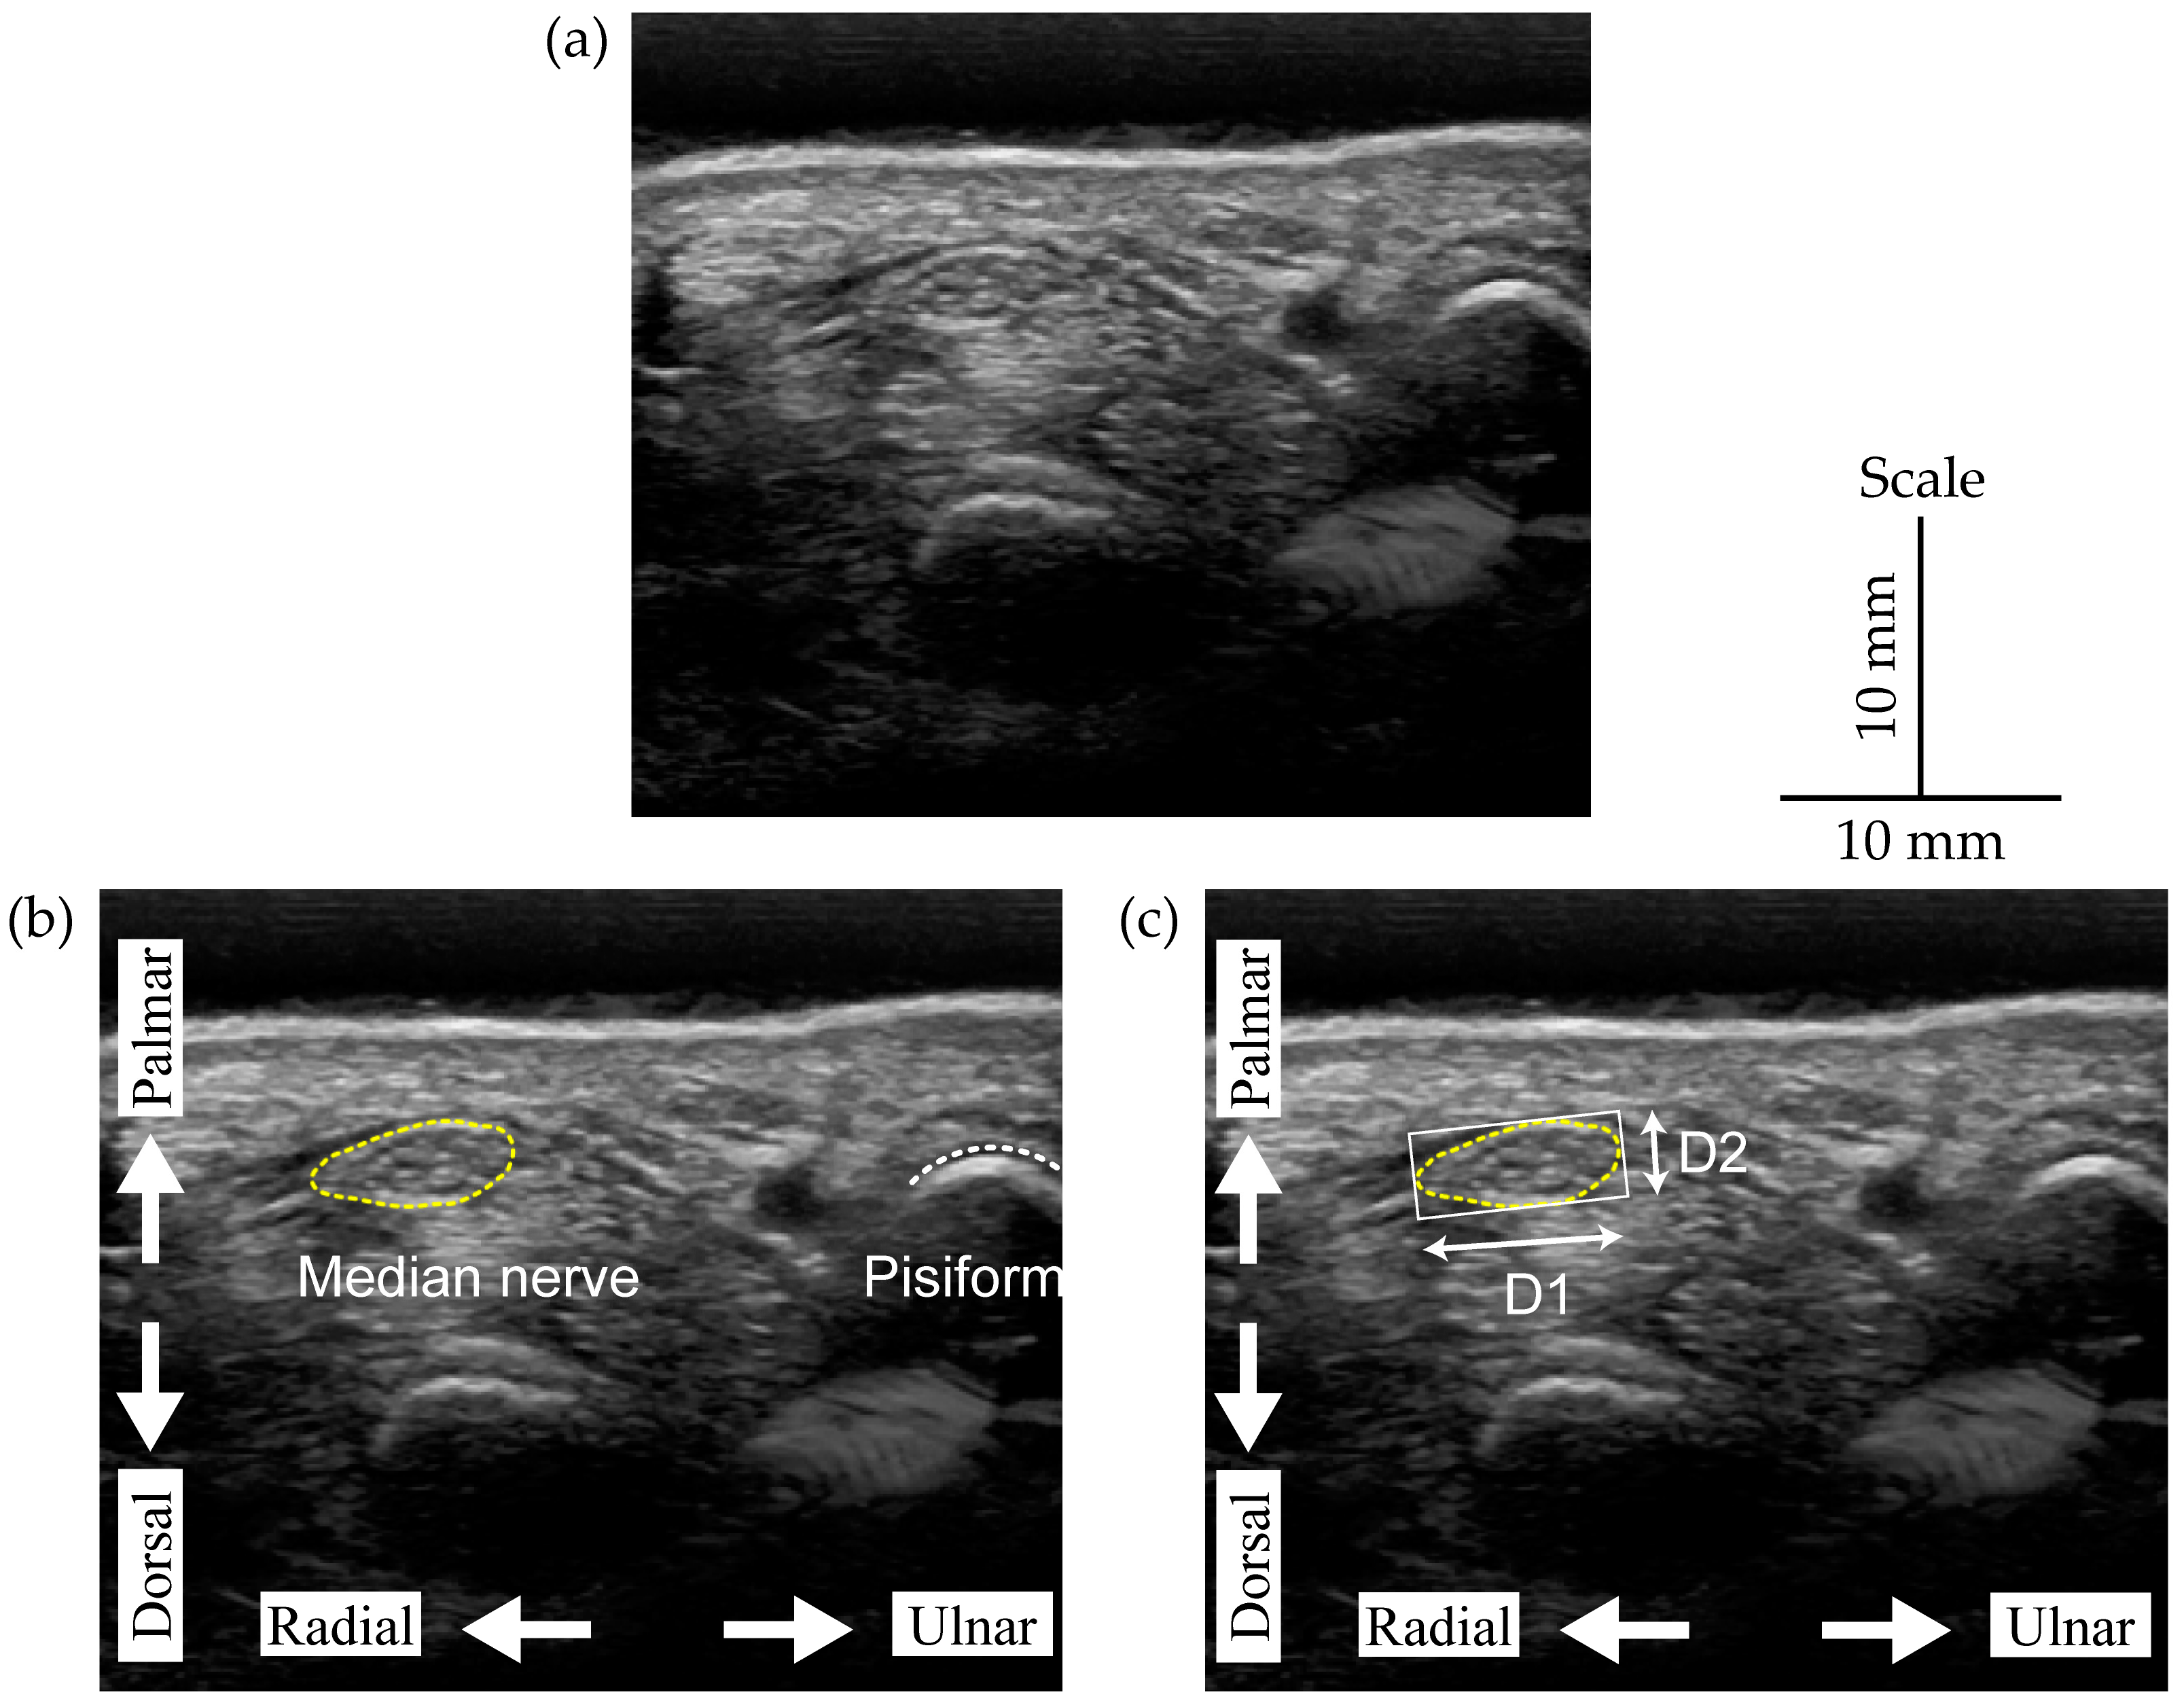

2.1. Ultrasound Image Acqusition and Dataset Preparation

2.2. Manual Annotation of the Median Nerve